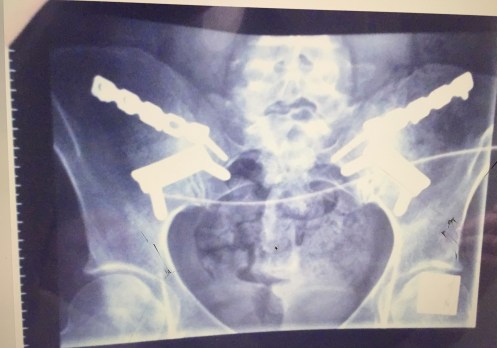

Sometimes you’re lucky to make it through basic surgeries no matter the age. Even if the surgery was perfect. Perfect hip operations, though no post care of the standard required, is stopping these active normal ‘elderly’ from living the next 10,20,30,40 years of their lives. Due to disrespect and lack of care.